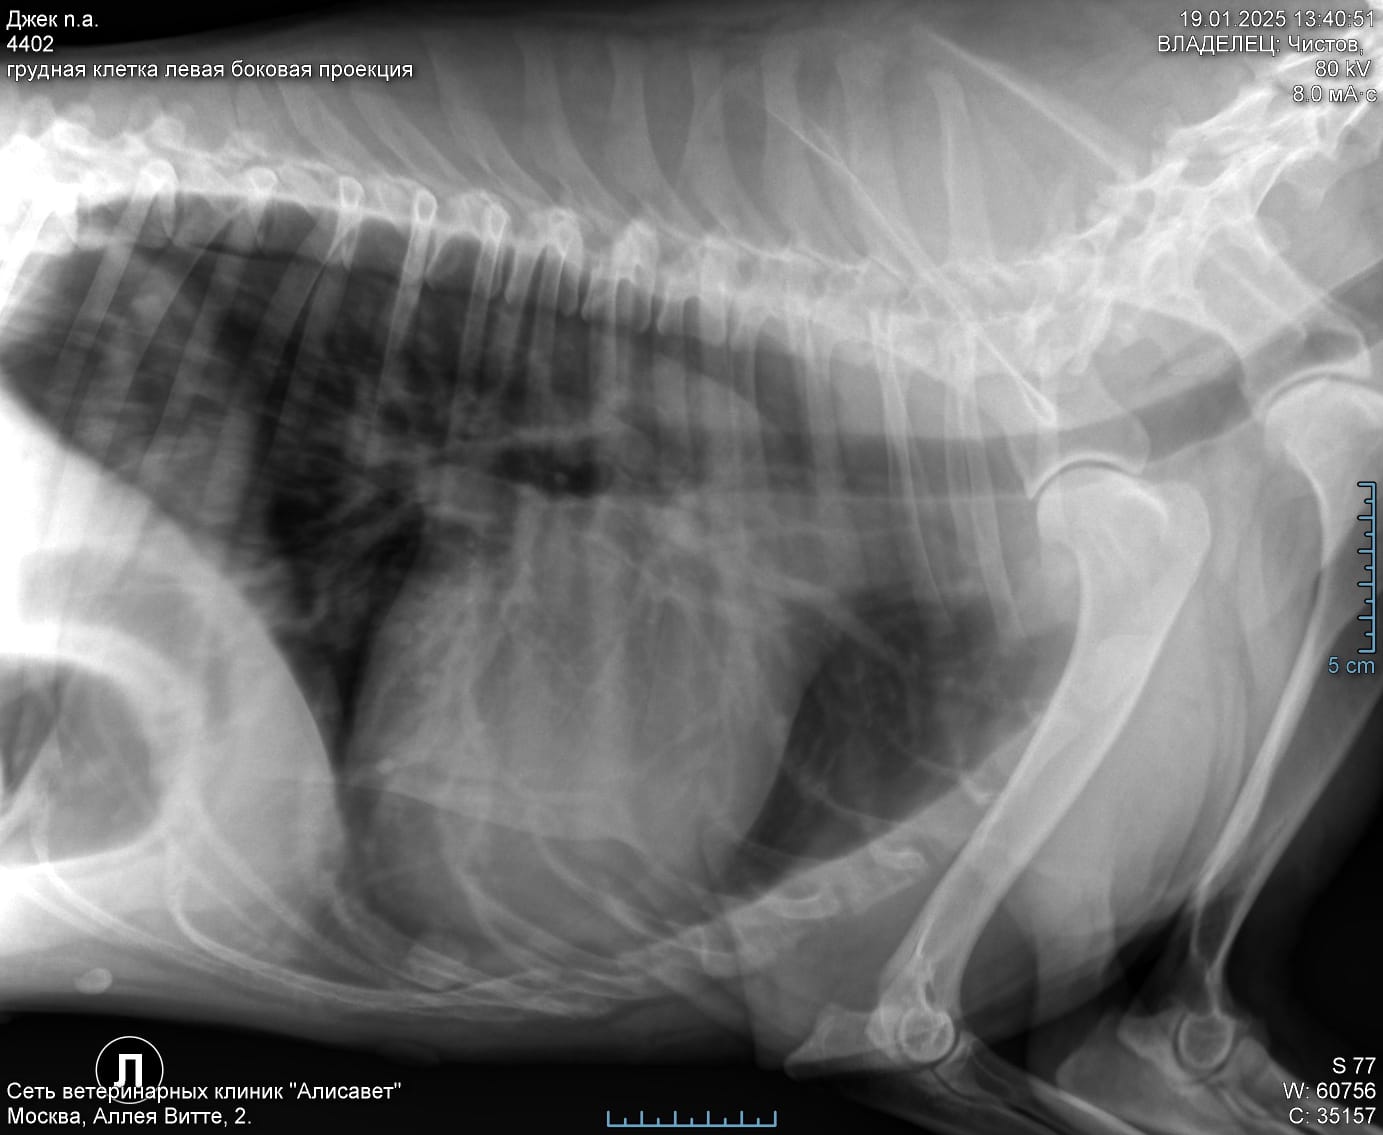

По сердцу и легким отводов нет